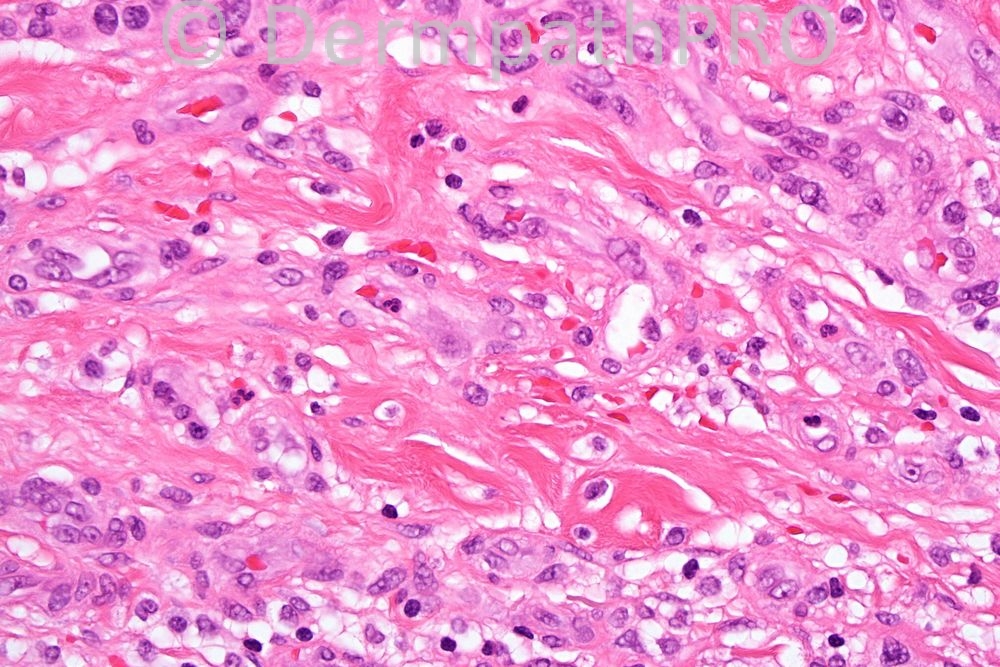

Female 30 years, lesion on thigh clinically hemangioma.